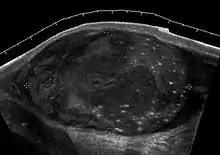

Teratoma Although teratoma is the second most common testicular tumor in children, it affects all age groups. Mature teratoma in children is often benign, but teratoma in adults, regardless of age, should be considered as malignant. Teratomas are composed of all three germ cell layers, i.e. endoderm, mesoderm and ectoderm. At ultrasound, teratomas generally form well-circumscribed complex masses. Echogenic foci representing calcification, cartilage, immature bone and fibrosis are commonly seen [Fig. 5]. Cysts are also a common feature and depending on the contents of the cysts i.e. serous, mucoid or keratinous fluid, it may present as anechoic or complex structure [Fig. 6].

Fig. 5. Teratoma. A plaque like calcification with acoustic shadow is seen in the testis.